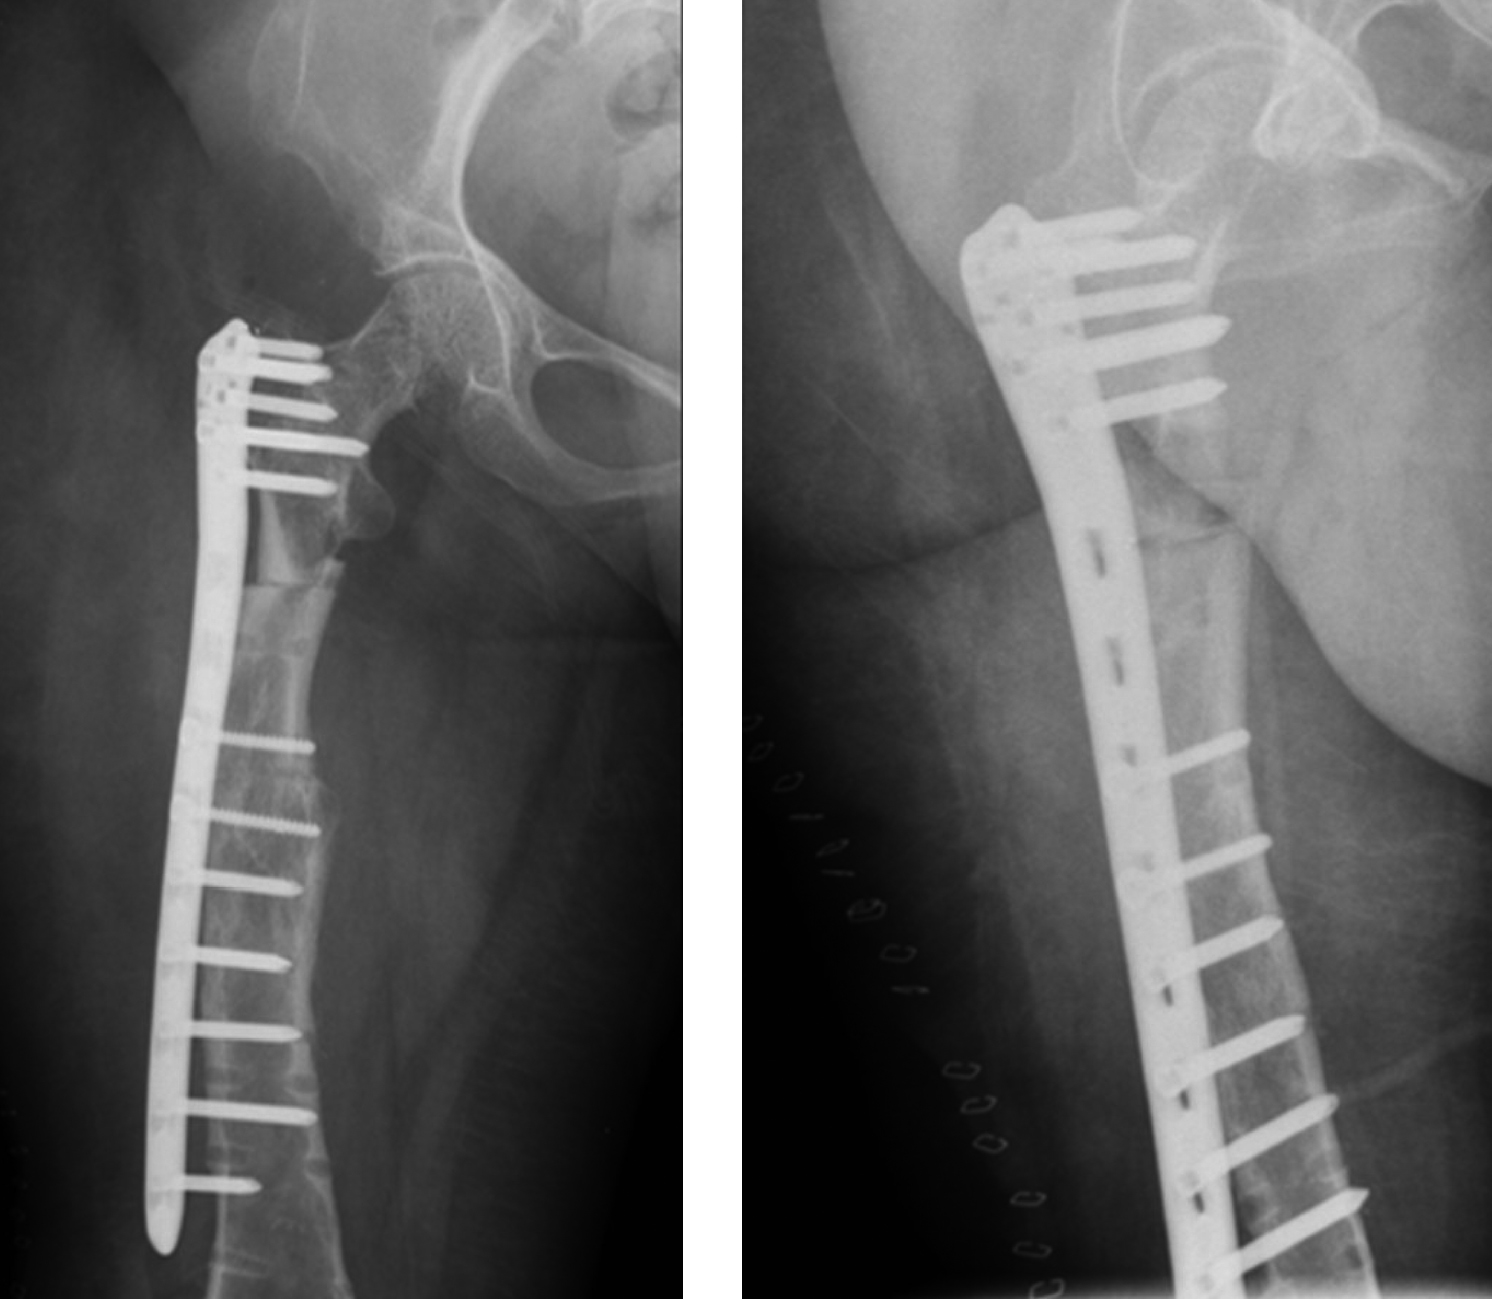

В связи с этим после стационарного обследования 29 января 2019 г. была выполнена операция — удаление винтов и пластины из правого бедра, экономная адаптирующая резекция на уровне периимплантного перелома, корригирующая деваризация и компрессионный остеосинтез блокируемой пластиной. Для остеосинтеза использовалась «перевернутая» контрлатеральная дистальная бедренная пластина в режиме динамической компрессии двумя кортикальными винтами. Для деконцентрации напряжения был использован монокортикальный дистальный винт. С учетом сниженной минеральной плотности кости количество винтов, введенных в каждый отломок, было больше, чем при остеосинтезе бедренной кости без остеопороза (рис. 4).

Рисунок 4. Рентгенограммы пациентки после операции удаления имплантатов, корригирующей остеотомии проксимального отдела правой бедренной кости и остеосинтеза блокируемой пластиной.

В послеоперационном периоде пациентка наблюдалась амбулаторно у генетика, эндокринолога и травматолога-ортопеда МОНИКИ. В процессе наблюдения отмечена положительная рентгенологическая динамика сращения (рис. 5).